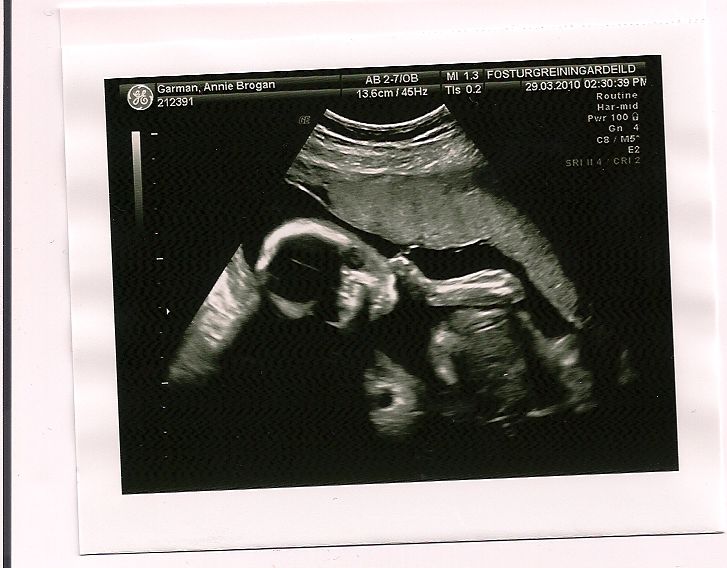

I never knew that going to an ultrasound could be such a frightening experience until today, nevertheless I am thankful that such technology allows us to prepare ourselves for the difficult time that appears to be ahead.

After the ultrasound technician was not satisfied with what she could see regarding the baby’s heart she suggested it might be good to have the doctor take a look. We moved to a new room and met the doctor as he began to study the baby’s heart to see if there was anything to be concerned about. Any explanation that begins…”The problem with your baby’s heart…” is bound to put a lump in your throat, but we gathered our wits to be able to process the explanation that we received and I will try to summarize for you.

Our little girl (yes it’s a girl) has a heart defect. The initial diagnosis is that it is either critical pulmonary stenosis (more likely) or pulmonary atresia with intact ventricular septum (possibly). Either way it will require a procedure immediately after birth. Only time will tell whether the condition will be treatable with a catharization or require a more extensive surgery. We will return to the doctor after our vacation and he hopes to be able to see better exactly what the situation is.